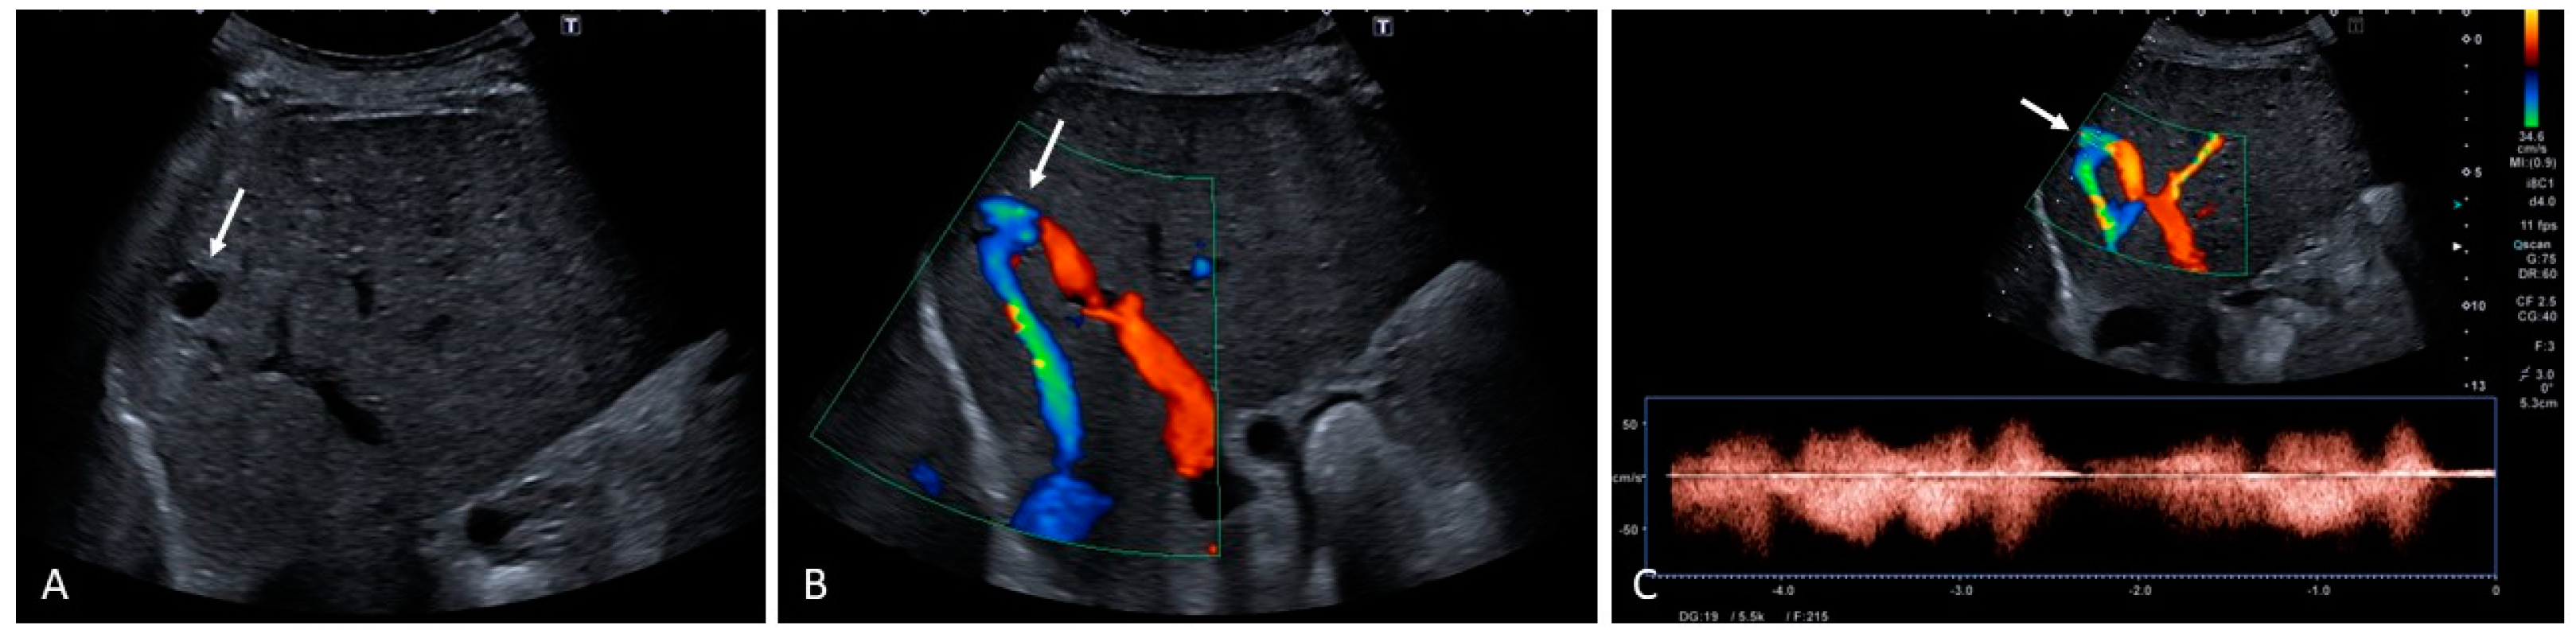

6. Vascular Malformations

- Hepatic artery dilatation > 4 mm.

- Normally, the diameter of the hepatic artery is smaller than that of the splenic artery; thus, an inversion of this relationship may be an early sign of liver VM.

- An increased velocity within the hepatic artery, with a peak flow velocity greater than 100 cm/s.

- Peripheral subcapsular ‘spots’ on power or color Doppler with high arterial blood flow velocities and low resistive indices are suggestive of small peripheral VMs.

- Other ultrasound findings include tortuous intrahepatic tubular structures communicating between the portal venous branches and the hepatic venous branches, tubular structures parallel to the portal branches representing dilated arterial branches, and vascular shunts. Arterio-systemic and arterio-portal shunts have low resistive indices, and arterio-portal shunts may be accompanied by the presence of portosystemic collaterals. Furthermore, arterio-systemic shunts can lead to arterialization, dilation, and turbulent flow of the portal vein and hepatic veins.